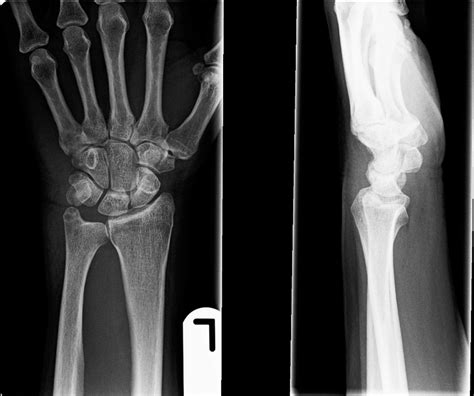

Diagnosing Wrist Fractures

Diagnosing a wrist fracture typically involves a physical examination and imaging tests. A healthcare provider will assess the wrist's range of motion, stability, and tenderness. Imaging tests, such as X-rays, are essential for confirming the diagnosis and determining the extent of the fracture. In some cases, a CT scan or MRI may be ordered to get a more detailed view of the fracture and surrounding tissues.